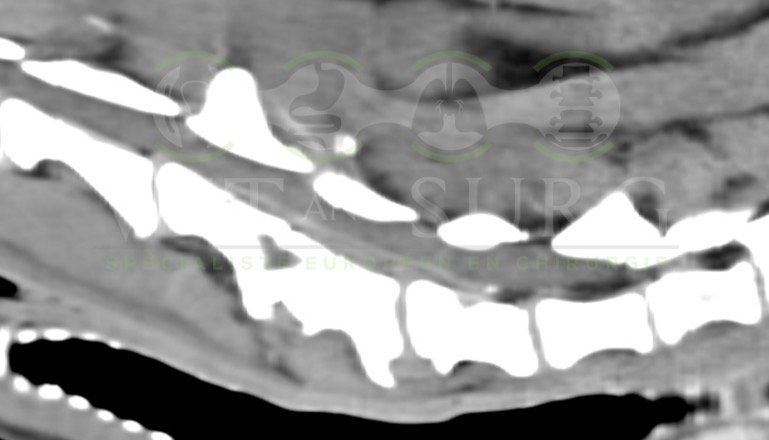

Hernie discale chez un bouledogue de 5 ans

Georges est présenté pour une paralysie des deux membres postérieurs.

Le scanner du rachis révèle une hernie discale en L3-L4 comprimant sévèrement la moelle épinière.